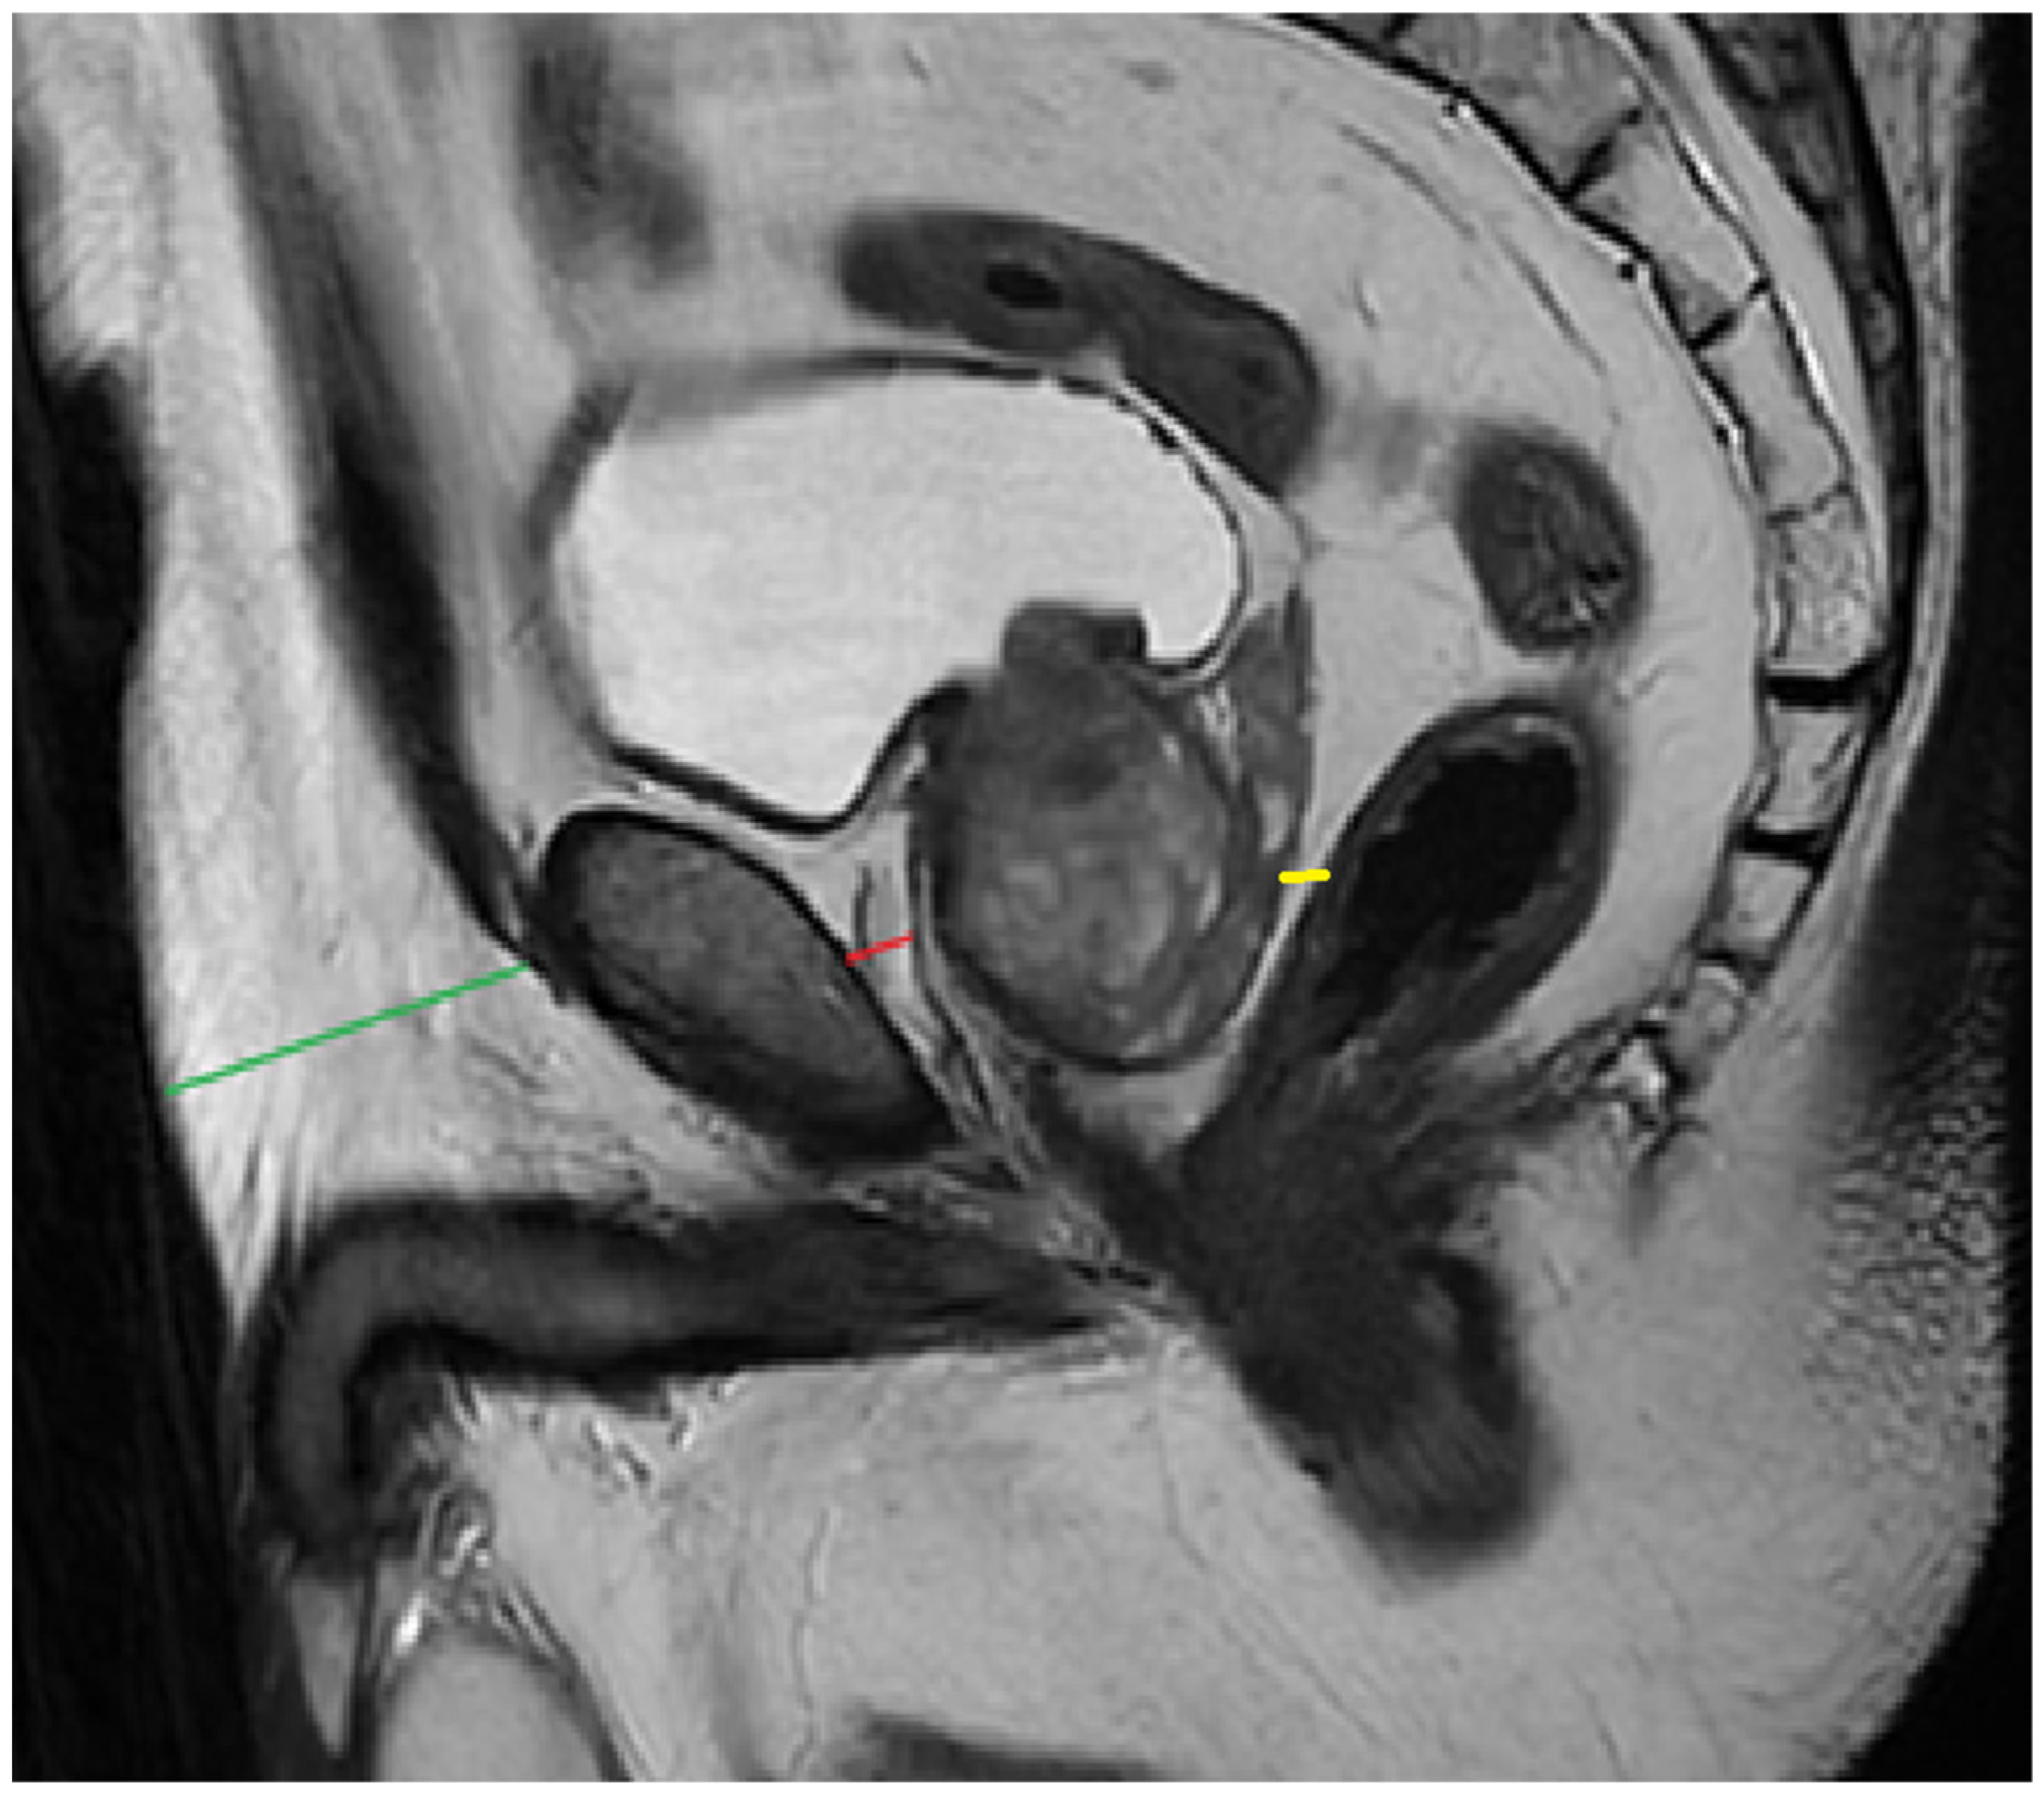

For all patients, PPAT thickness (PPATT), posterior periprostatic adipose tissue thickness (PPPATT), and subcutaneous adipose tissue thickness (SATT) were measured on T2-weighted MRI images by a radiologist with experience in prostate MRI using RadiAnt DICOM Viewer 2025.2 (Medixant: Poznań, Poland, https://www.radiantviewer.com/). T2W images not only provide clear visualization of fat distribution, but also represent the most appropriate sequence for such measurements and are one of the core components of biparametric MRI protocols. In addition to these linear measurements, volumetric analysis of periprostatic adipose tissue was also performed, providing a more comprehensive evaluation of fat distribution. This dual approach allowed for both simplified morphometric assessment and a more nuanced spatial quantification of adiposity. The image below represents a schematic sagittal MRI view of the male pelvic region (Figure 1).

PPATT was measured as the shortest vertical distance from the pubic symphysis to the anterior surface of the prostate on midsagittal images; SATT was measured on the same slice as PPATT, defined as the shortest vertical distance from the pubic symphysis to the overlying skin, while PPPATT was measured as the shortest distance from the posterior surface of the prostate and anterior wall of the rectum. The images below represent the visual explanation of these measurements (Figure 2 and Figure 3).

Figure 2. Measurement of PPAT (red line), posterior PPAT (yellow line), and SATT (green line) on a midsagittal view, T2 sequence, on a prostate MRI categorized as PI-RADS 2, showing a prostate containing a well-defined prostatoc cyst.

Bioengineering 12 00831 g002